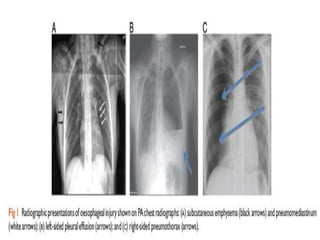

DIAGNOSIS

• Radiology Plain

- Neck X-ray lateral view

- Chest X-ray PA view

- Abdominal X-ray erect